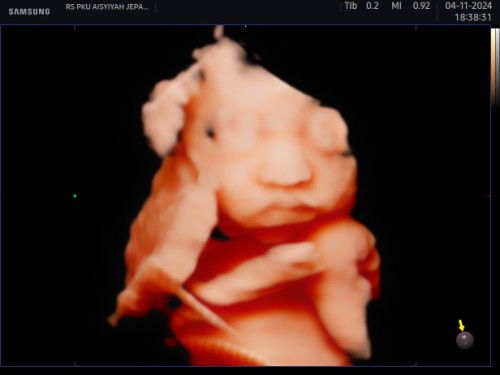

Bunda yang udah mengalami perut kenceng, pliiss jgn di biarin yaa. Nanti kaya saya, saya dari 28minggu perut sering kenceng konsul ke bidan dan obgyn katanya normal cuma kontraksi palsu tp ternyata itu bisa menyebabkan ketuban pecah dini!! Sekarang saya usia 33minggu ketuban rembes dan perut kenceng semakin sering tapi tanpa di sertai pembukaan dan mules2, usg alhamdulillah air ketuban masih cukup, dan akhirnya di suntik pematang paru paru 4kali.. #sehatsehatanakibu